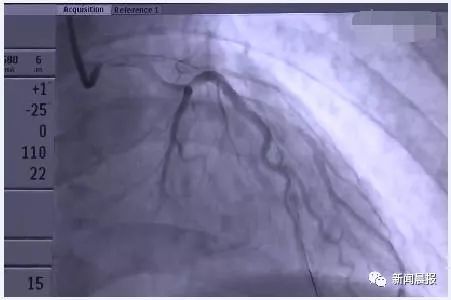

入院后医生立即作出判断,

必须要做急诊手术,

医生经过4个小时的及时抢救,

陆先生才从“死神”掌心惊险挣脱。